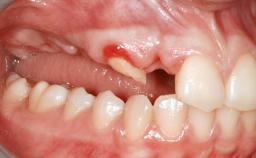

Iliac and Calvarial Bone Blocks for Onlay Grafting of a Severely Resorbed Edentulous Maxilla

A 45-year-old woman with a completely edentulous maxilla was referred to evaluate the possibility of rehabilitation with an implant-supported prosthesis. This patient was healthy and a non-smoker. She had been wearing a maxillary complete denture opposing a natural mandibular dentition since her twenties. This situation had resulted in progressive resorption of the alveolar ridge, repeatedly creating a need for relining the denture. Twenty years later, despite multiple adaptations and the use of “glues” the denture was unstable and causing the patient psychological and functional discomfort.

| Soft Tissue Anatomy | Intact | Defective | |

| Bone Volume | Horizontally and vertically sufficient | Horizontally deficient | Deficient vertically or deficient vertically AND horizontally |